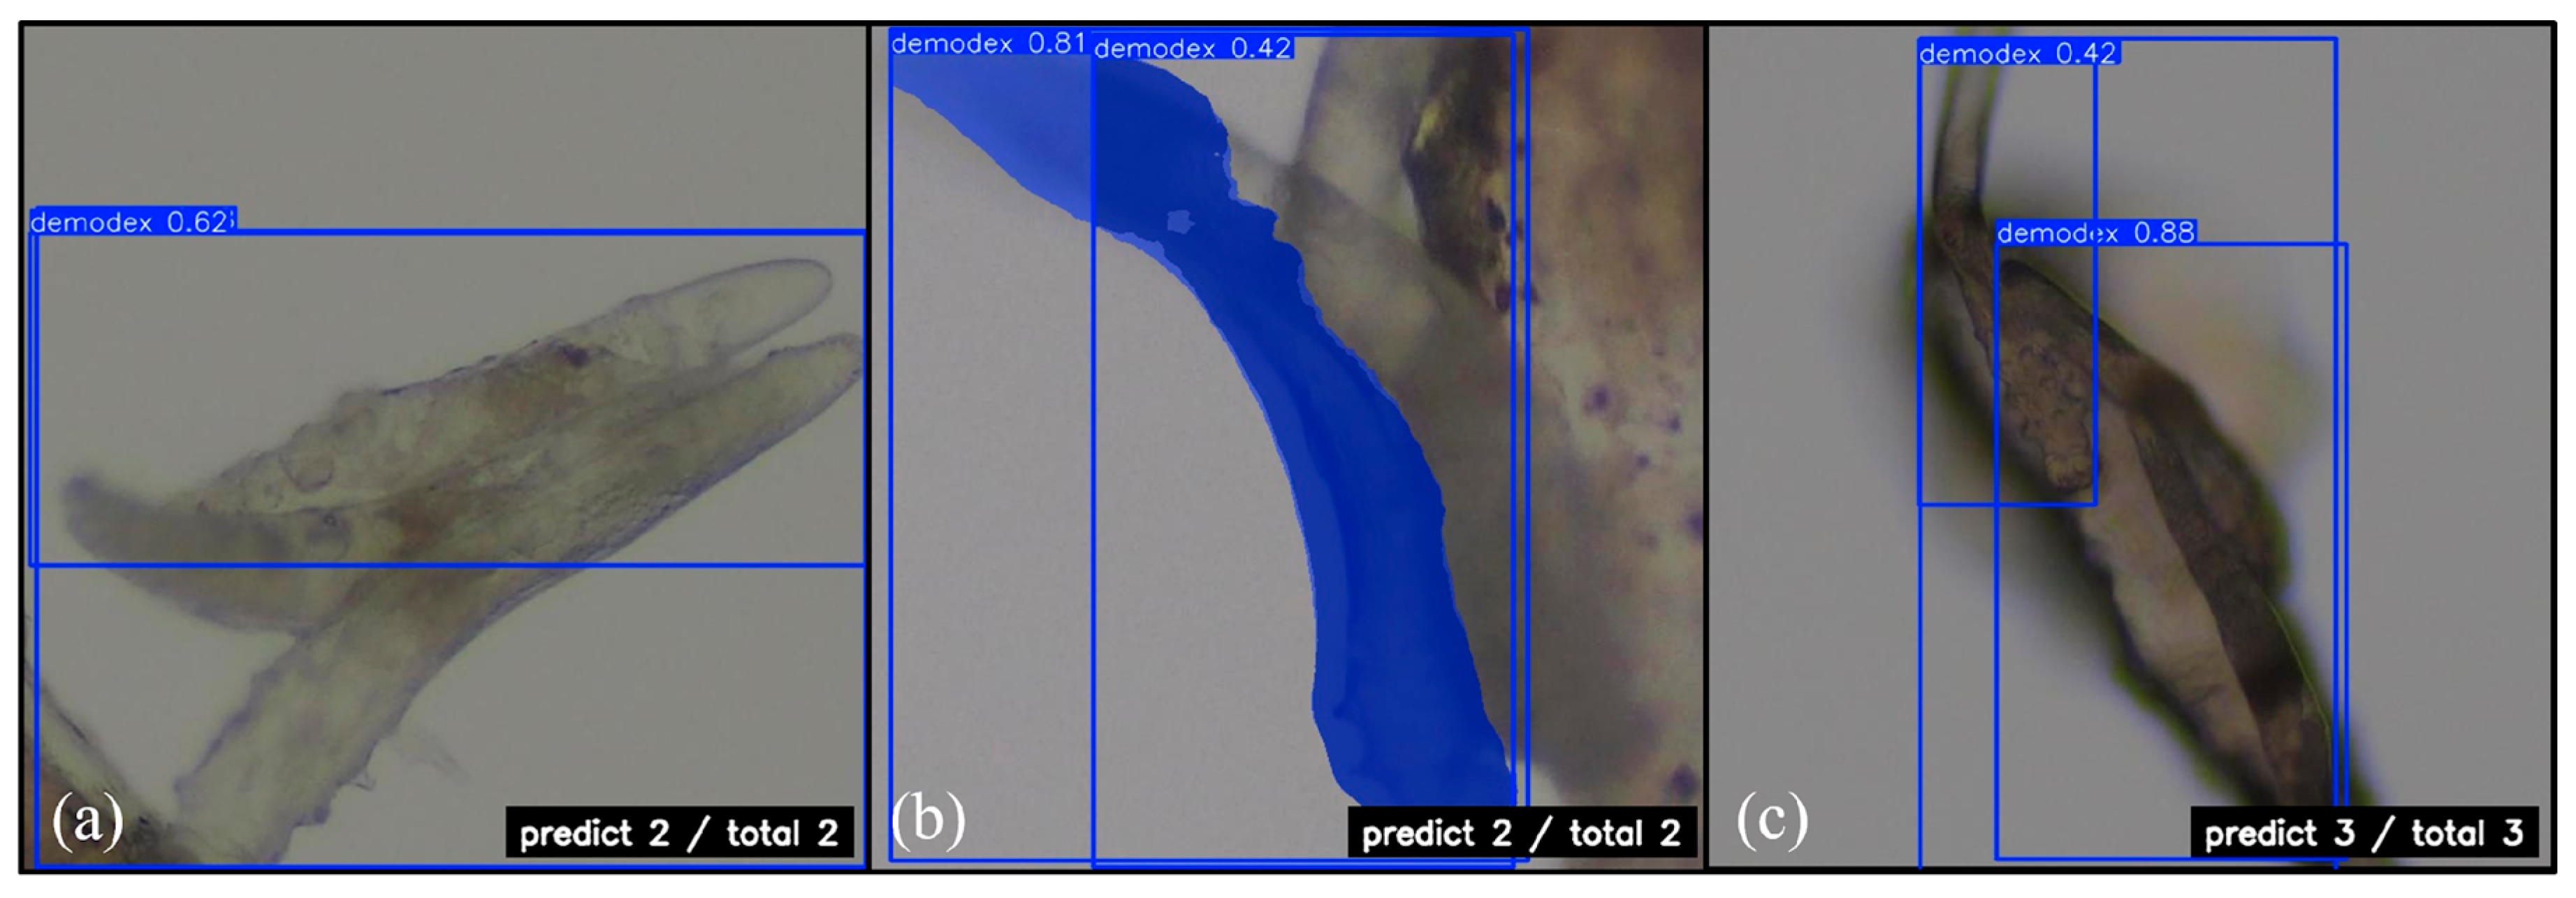

3.1. YOLOv11 Boxing

3.2. YOLOv11 Segmentation

3.3. RT-DETR

3.4. Grad-CAM Feature Evaluation